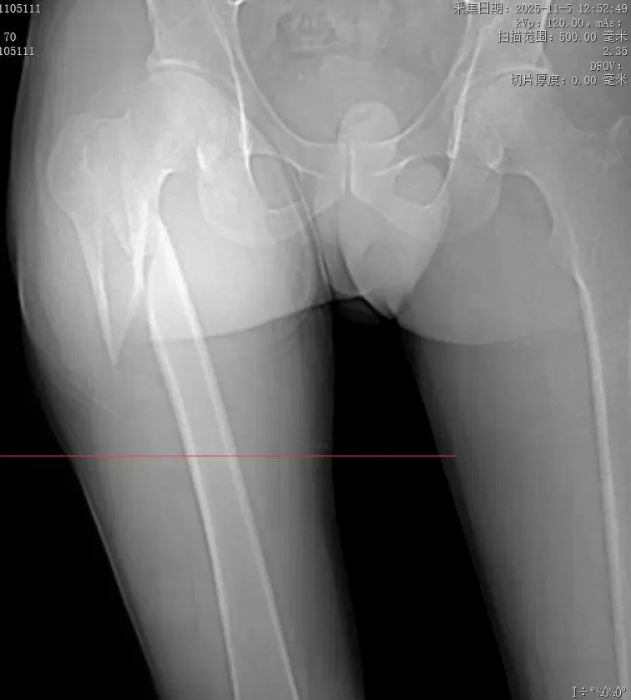

骨科医师团队随即启动专科诊疗流程。经急诊影像学检查,确诊为“股骨粗隆下骨折”——这是骨科领域公认的复杂骨折类型,愈合难度大、治疗风险高。该部位是下肢力量传导的关键节点,肌肉附着多、应力集中,骨折后易出现三维畸形,复位困难,且不愈合率居高不下,再叠加患者此次高能量损伤导致的严重移位,若治疗不当,不仅可能导致终身残疾,更会让患者陷入长期病痛折磨。

面对这一公认的“硬骨头”病例,我院骨科团队迅速组织病例研讨,结合患者伤情特点与影像学检查结果,经综合评估后决定采用“闭合复位内固定术”这一精准诊疗方案。 团队的底气在此刻尽显——骨科路江鸿主任牵头明确治疗方向。“我敢闭合你就敢愈合”,这并非一句空泛的口号,而是源于团队多年深耕疑难骨折诊疗的技术积淀:针对该骨折治疗中“复位难、固定难、愈合难”的三大核心痛点,团队已形成成熟的诊疗方案,更在闭合复位内固定技术上积累了丰富经验,这是对自身实力的绝对自信,更是对患者生命健康的责任担当。